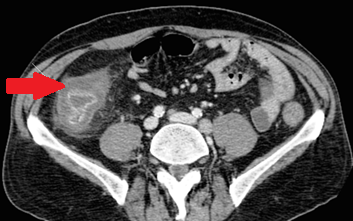

CT κοιλίας. Κόκκινο βέλος — Τυφλίτιδα. Σημαντική πάχυνση τοιχώματος τυφλού (Ευγενική παραχώρηση Dr. V. Penopoulos)